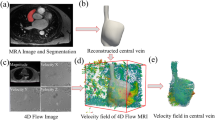

S-AVS is performed as follows (Fig. 1). A dedicated 5-Fr or 6.5-Fr catheter for the left adrenal vein is inserted into the left adrenal central vein via the left femoral vein. Then, a dedicated 5-Fr or 6.5-Fr catheter for the right adrenal vein is inserted into the right adrenal central vein via the right femoral vein. Next, microcatheters are inserted into the intra-adrenal first-degree tributary veins on the bilateral adrenal glands through the catheters via a coaxial method and blood samples are obtained via gentle aspiration from both the adrenal veins and their tributaries. However, S-AVS has some technically difficult points. First, it is sometimes difficult to insert a microcatheter into the intra-adrenal tributary veins. In addition, even if the insertion can be achieved, it is often the case that little blood passes through the microcatheter despite the application of a suction pressure. In such cases, it is suspected that the hole of the catheter tip is occluded by the deformation of the vein due to the suction pressure.

A three-dimensional fluid–structure interaction (FSI) simulation was performed using commercial finite element software (COMSOL Multiphysics 5.0; COMSOL, Massachusetts, USA). The FSI simulation appears to be more realistic than the conventional CFD method of simulating a vein that is soft and easily deformed. In the human body, veins are not present in isolation but are instead surrounded by connective, muscular, and other biological tissues. Therefore, in this study, a computational model of a vein surrounded by muscular tissue and catheters inserted into the vein was constructed (shown in Fig. 2). The outer and inner diameters of the vein and its wall thickness were 0.9 mm, 0.6 mm, and 0.15 mm, respectively. The outer and inner diameters of the catheter and its wall thickness were 0.6 mm, 0.5 mm, and 0.05 mm, respectively. The geometry of the muscular tissue block was 2 mm × 2 mm × 20 mm. In this study, the blood was assumed to be an incompressible Newtonian fluid with a laminar flow and to have a viscosity of 0.0035 Pa s and a density of 1050 kg/m3. These values are typical for blood flow models [2]. The Young modulus and Poisson ratio of the vessel wall were 2 × 103 Pa [3, 4] and 0.50, respectively, and those of the catheter wall were 169 × 109 Pa and 0.22, respectively. The vessel wall was assumed to be incompressible and to have a Poisson ratio of 0.5. In this study, the deformation of the catheter was not taken into consideration to reduce the computational cost. Polyamide and polyamide-based polymers are usually used for commercial catheters. In this study, the Young modulus of the catheter wall was set higher than the actual value so that the wall would not deform within the range of pressures used in the study. No-slip boundary conditions were applied at the walls. The model was fixed on the outlet side of the muscle block and on the outlet side of the catheter. The Young modulus and Poisson ratio of the muscular tissue around the vessels were 3.3 × 106 [19] and 0.50, respectively. The muscle was assumed to be incompressible with a Poisson ratio of 0.5. The velocity of the blood flow at the outlet was 85 mm/s, and the pressure at the inlet was 0 Pa. Makita reported that approximately 1 ml of blood can be aspirated per minute using a commercial microcatheter with two notches [8]. The outflow rate was set according to these clinical data. The mesh consisted of approximately 660,000 tetrahedral elements with approximately 190,000 elements for the muscular tissue, approximately 230,000 elements for the vessel wall, approximately 11,000 elements for the catheter, and approximately 230,000 elements for the blood (Fig. 3). We conducted a series of mesh dependency studies with the total mesh number being increased from 110,000 to 660,000. Because the results did not differ greatly between meshes with sizes of 440,000 and 660,000, we adopted a mesh with a size of 660,000. The convergence criterion was 5 × 10−4. The term mesh is commonly used in computational analyses including in CFD. To analyze fluid flows, the flow domains are divided into smaller subdomains. The subdomains are called elements, and the collection of all the elements is called the mesh. The convergence criterion is the threshold value for terminating the iterative computation.

In analysis 2, catheters having different notch shapes were compared (Fig. 5). There were six notch shapes considered: no notch, two 1/4-circular notches, two 1/3-circular notches, two semicircular notches, two 2/3-circular notches, and two 3/4-circular notches. The displacements along the y- and z-axes, the total average venous wall displacement, and the shear rate were evaluated.